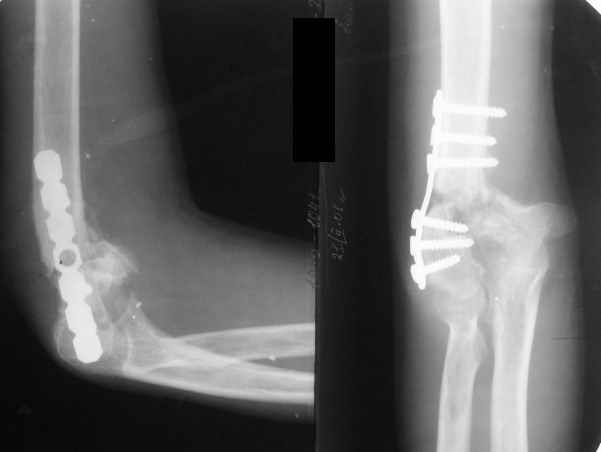

The recent x rays show established Non union with poor quality bone in the distal fragement. The joint is also appearing degenerate. In view of the multiple failed reconstructive surgeries, an Elbow replacement would seem reasonable.

However it would have to be a fully constrained one as there would be missing bone stock.

Obviously there is no elbow joint...the options are few: (from the worst to the "best"...if any)

3. Total elbow replacement (semi constrained - as no ligaments to stabilize the joint) - Coonrad-Morrey, Discovery - Biomet - considering his age there is limited indication for that procedure.